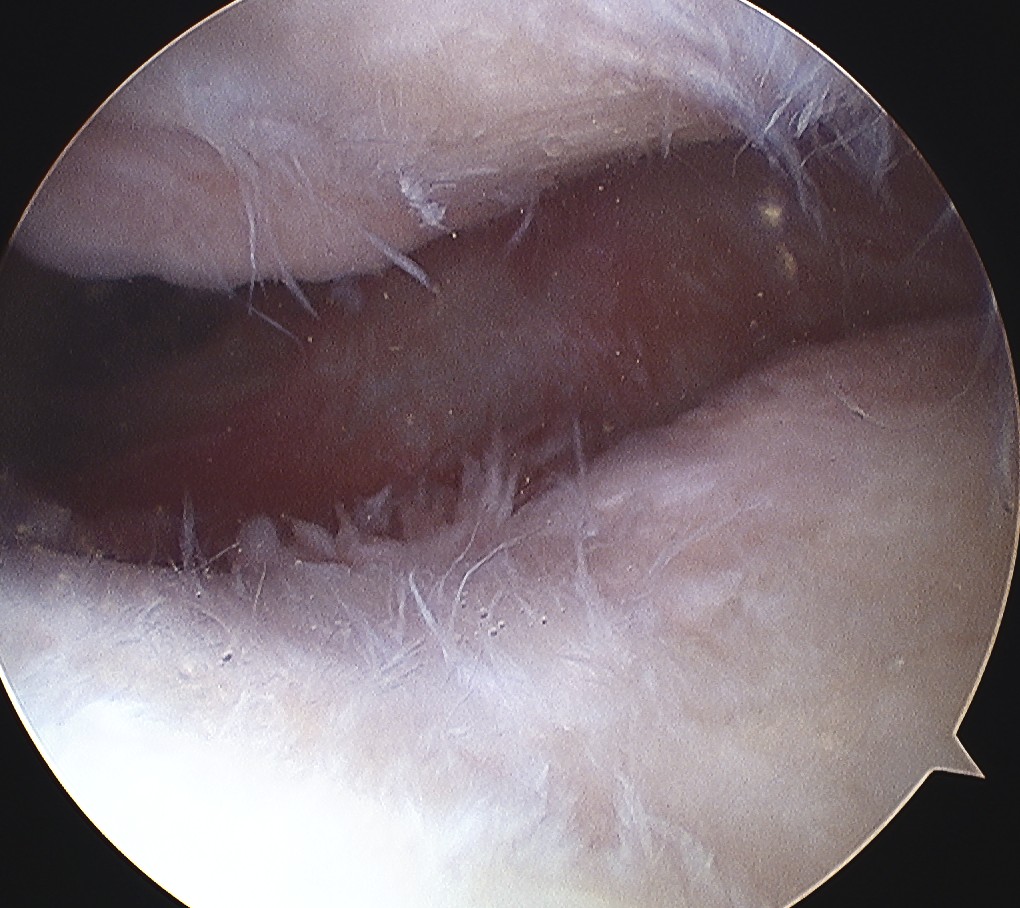

Arthroscopy

Patterns

Lateral facet - patella maltracking / trochlea dysplasia

Medial facet - patella dislocation and cartilage damage

Global - primary OA, patella fracture, obesity

Central trochlea - repetitive deep flexion

Medial facet OA Lateral facet OA